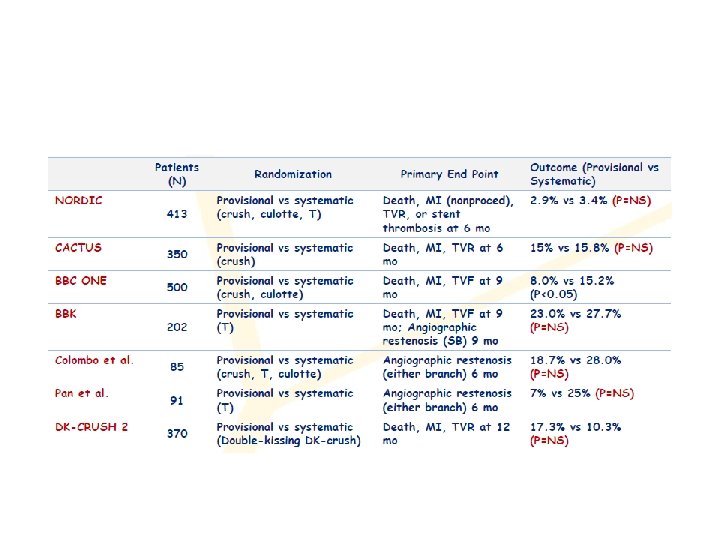

One vs two stents • • • Important trials NORDIC 2 BBC CACTUS

1. Nordic I: provisional T stenting as good as systematic side branch stenting 2. Nordic II: Culotte better than Crush 3. Cactus: provisional T stenting not worse than crush 4. BBC ONE: step wise approach with provisional T stenting better than initial complex procedures 5. Bad Krozingen: no difference provisional vs systematic T 6. Double Kiss Crush Study: DK Crush better than conv. crush Steigen Circulation 2006; 114: 1955; Erglis TCT 2008; Hildick-Smith TCT 200 Ferenc EHJ 2009; Chen JInterv Cardiol 2009; 22: 121 -27